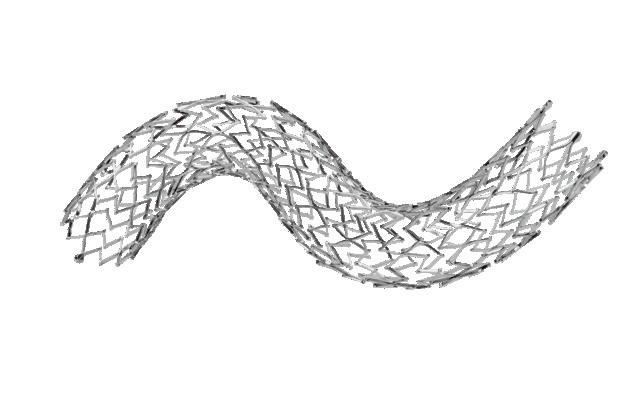

Stenting of the SFA for intermittent claudication yields quality-of-life benefits out to 36 months

In a recent study of patients with intermittent claudication (IC) caused by isolated superficial femoral artery (SFA) lesions, researchers found that primary stenting conferred benefits in health-related quality of life (HRQoL) at 36 months from treatment compared with best medical therapy (BMT) alone, which were lost at the 60-month mark, where a high crossover rate affected the power of the final analysis.

RESULTS OF THE STUDY

were recently published online in the European Journal of Vascular and Endovascular Surgery (EJVES). The investigators—led by Thordur Gunnarsson (Lund University, Lund, Sweden)— highlight their previous finding that primary stenting of the SFA in IC increased HRQoL after 12 and 24 months in this trial. The current paper, they note, presents an extended followup of HRQoL 36 and 60 months after randomisation.

This was a multicentre randomised controlled trial conducted at seven vascular clinics in Sweden between 2010 and 2020, which included 100 patients randomised to either primary stenting and BMT (n=48) or BMT alone

(n=52) followed for 60 months.

Gunnarsson et al detail that HRQoL—which they assessed using the Short-Form Health Survey (SF-36) and EuroQoL 5 dimensions (EQ5D) 36 and 60 months after randomisation— was the primary outcome. Walking Impairment Questionnaire (WIQ) score, reinterventions, progression to chronic limb-threatening ischaemia (CLTI), amputation, and death were secondary outcomes.

The authors report that, at 36-month follow-up, the stent group (n=32) had “significantly better” scores in the SF36 domain Role Physical (RP, p=0.023) and the Physical Component Summary (PCS, p=0.032) compared to the control group (n=30), however, there was no

significant difference in EQ5D scores (p=0.523).

In addition, they reveal that WIQ was also “significantly better” compared to the control group (p=0.029) at 36 months.

At 60-month follow-up, Gunnarsson and colleagues found no significant difference in HRQoL between the stent (n=31) and the control group (n=32),

months and the 25% crossover from the control group to stent at 60 months “negatively affected the power of the analysis”. In future trials of invasive treatment of IC, they write, crossover and loss to follow-up “need to be taken into account”.